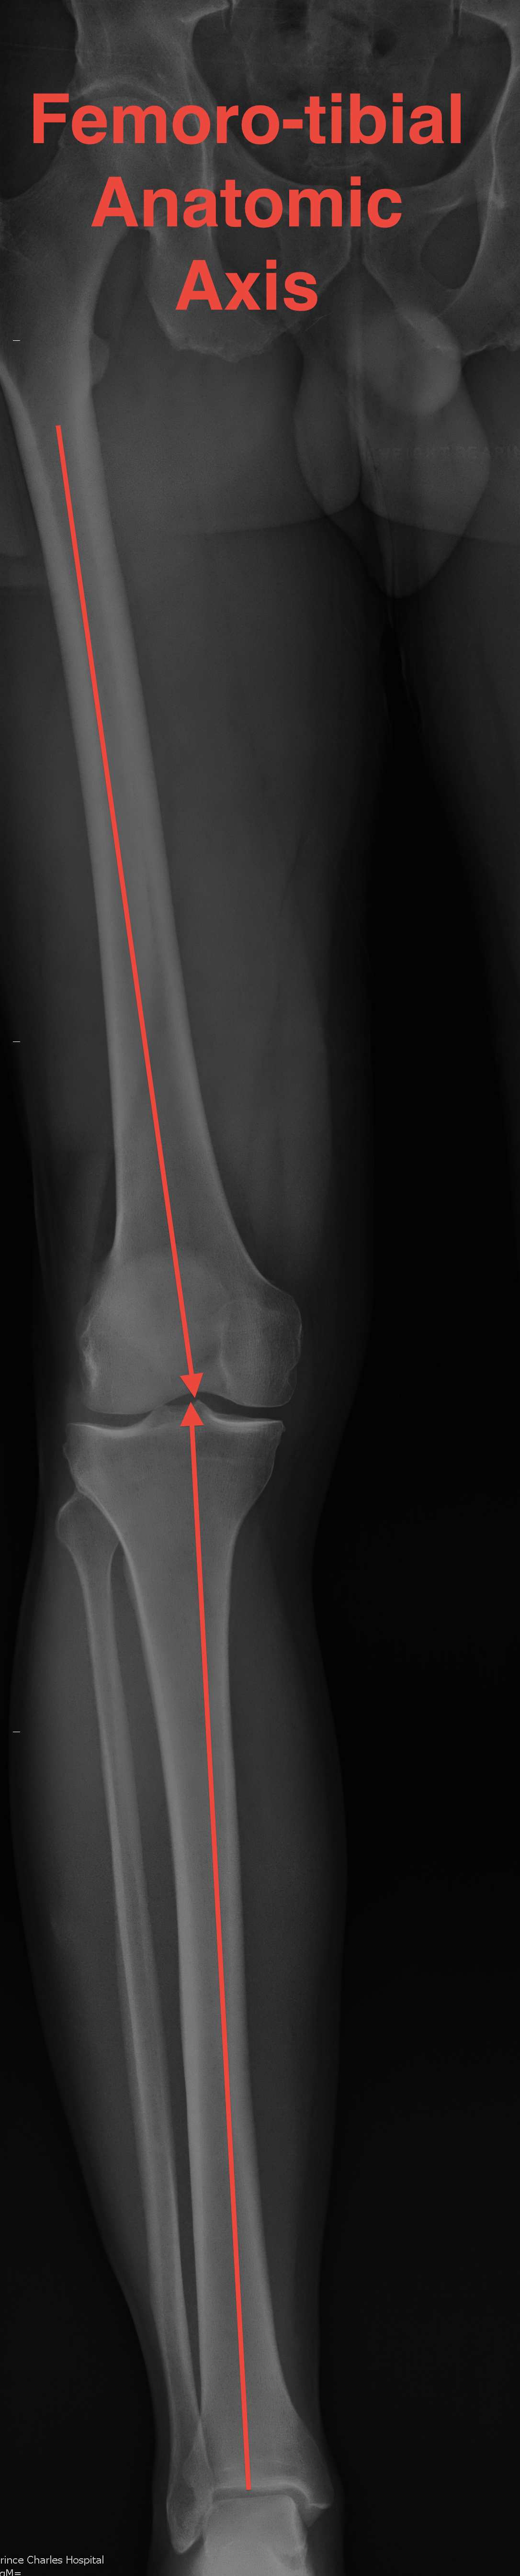

Anatomic Femorotibial axis

- anatomic axis of femur and tibia

- should be 6o +/-3o